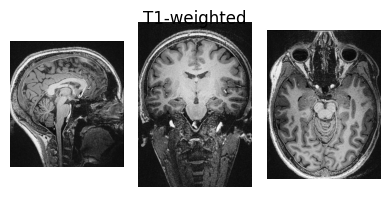

Inspect input data#

Here we define a function we will use to visualise NIfTI images so we can view some of the input data:

show_nii(glob("bids/sub-*/ses-*/anat/*mag*T2starw*nii*")[0], title="Magnitude", vmax=500)

show_nii(glob("bids/sub-*/ses-*/anat/*phase*T2starw*nii*")[0], title="Phase")

show_nii(glob("bids/sub-*/ses-*/anat/*T1w*nii*")[0], title="T1-weighted")